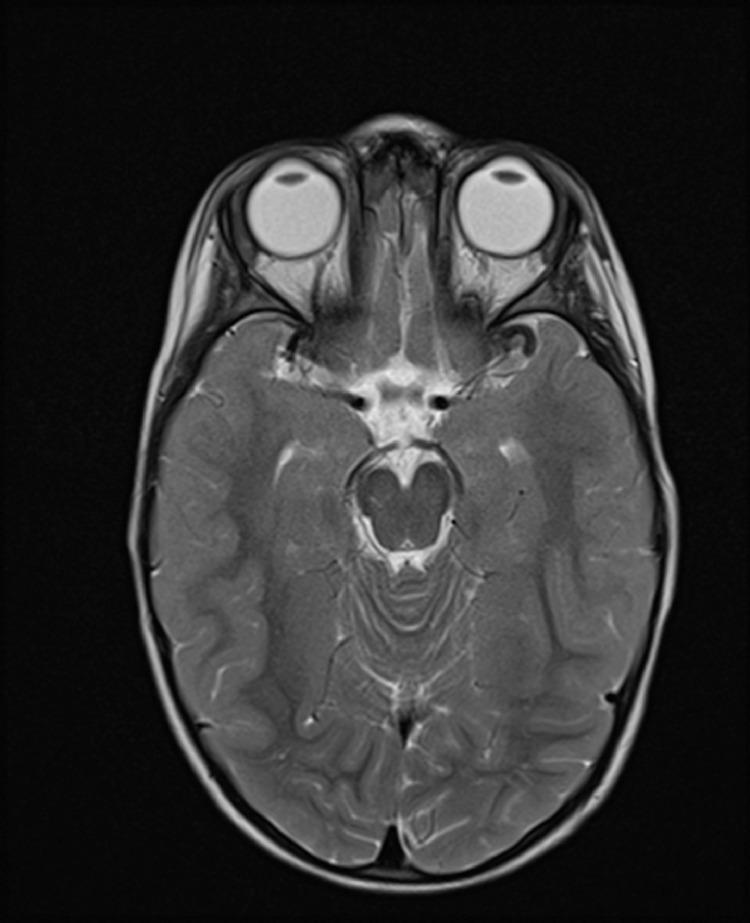

一名男孩的异位神经垂体:病例报告及文献复习

Ectopic neurohypophisis in a boy: A case report and review.

Ectopic neurohypophysis is rare anomaly which is characterized by ectopic location of posterior pituitary lobe (neurohypophysis), pituitary stalk abnormalities and association with dysfunction of anterior lobe related with growth hormone or with multiple dysfunction of the same.We present a rare case of posterior ectopic pituitary and pituitary stalk hypoplasia isolated in 2 year-old male patient.

摘要

异位神经垂体是一种罕见的异常情况,其特征为垂体后叶(神经垂体)异位、垂体柄异常,并伴有与生长激素相关的前叶功能障碍或多种功能障碍。我们报告了一例罕见的2岁男性患者孤立性垂体后叶异位和垂体柄发育不全的病例。